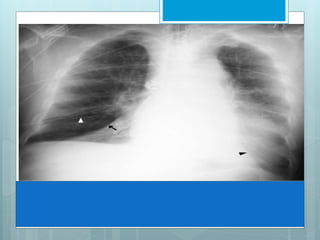

LUL Collapse

Luftsichel, an indirect sign of LUL collapse.

 Its Crescent of aerated lower lobe.

 This represent an incomplete major fissure pulled

forward by atelectatic upper lobe, interposed between

atelectasis & aortic arch.

 Left lower lobe basilar segmental arteries are elevated

and clearly visible in retrocardiac location.

Note the

increased

opacification of

left upper lung

field with

elevation of left

hemi-diaphragm.

In addition,

there is lucency

adjacent to the

aorta.

This is the

Luftsichel sign,

representing an

over-expanded

right lower

lobe.